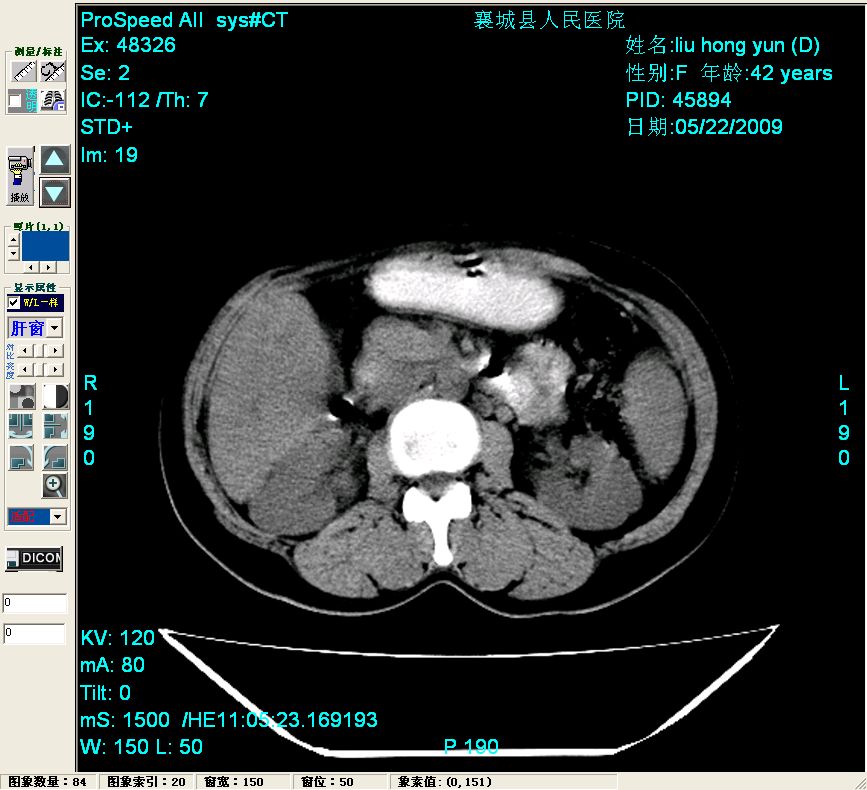

增强:

增强动脉期前述低密度区轻度早其强化,门脉期强化程度显著增高,延期扫描强化程度下降,但仍为相对高密度影

胰头部见结节状高密度影,其前方略可分辨扩强胆部管,平扫到增强始终有,但现在尚难与胃肠造影剂鉴别.

结合病史考虑,1现在引起黄疸体征的原因应该是胆总管胰段结石阻塞,建议局部胃肠造影剂排空后复查.

胆总管末端结石伴肝内胆管扩张合并结石!另:不除外合并胆系感染!

1)肝内胆管结石,胆总管末端结石伴肝内胆管扩张。2)肝左叶及肝右叶前段增强前后之异常表现,考虑炎性改变,不排除胆管细胞癌。

1)肝内胆管结石,胆总管末端结石伴肝内胆管扩张。2)肝左叶及肝右叶前段增强前后之异常表现,考虑炎性改变,不排除胆管细胞癌。3)脾大。